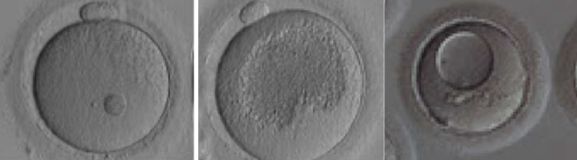

成熟的卵子大致为圆形,直径约130um。主要有三个部分组成:

1、最外面的环状结构是透明带,为卵子提供安全的屏障,在受精过程中防止多条精子同时进入卵子而导致多精受精,并在早期发育过程中对维持胚胎的立体结构发挥重要的作用。

2、卵母细胞,也就是卵子的最核心部分,与精子结合形成受精卵进而发育为胚胎。

3、第一极体的出现则意味着卵子已经发育成熟,做好了迎接精子受精的准备。

正常形态的成熟卵子应该为圆形、胞浆均匀、颗粒均匀、卵周隙内无杂质、第一极体形态正常以及透明带形态正常。在试管婴儿助孕中,卵母细胞的评分与临床妊娠结局有一定的相关性。

人的卵母细胞在胎儿出生时一直处于休眠状态,青春期开始逐渐进入成熟发育的阶段。此时的卵母细胞核较大,称为生发泡,即GV期卵子。在排卵前的36-48小时,生发泡破裂,这个阶段的卵子称为MI卵子。LH峰值后36-40小时,卵子完成减数分裂,排除第一极体,发育成熟为MII卵子。